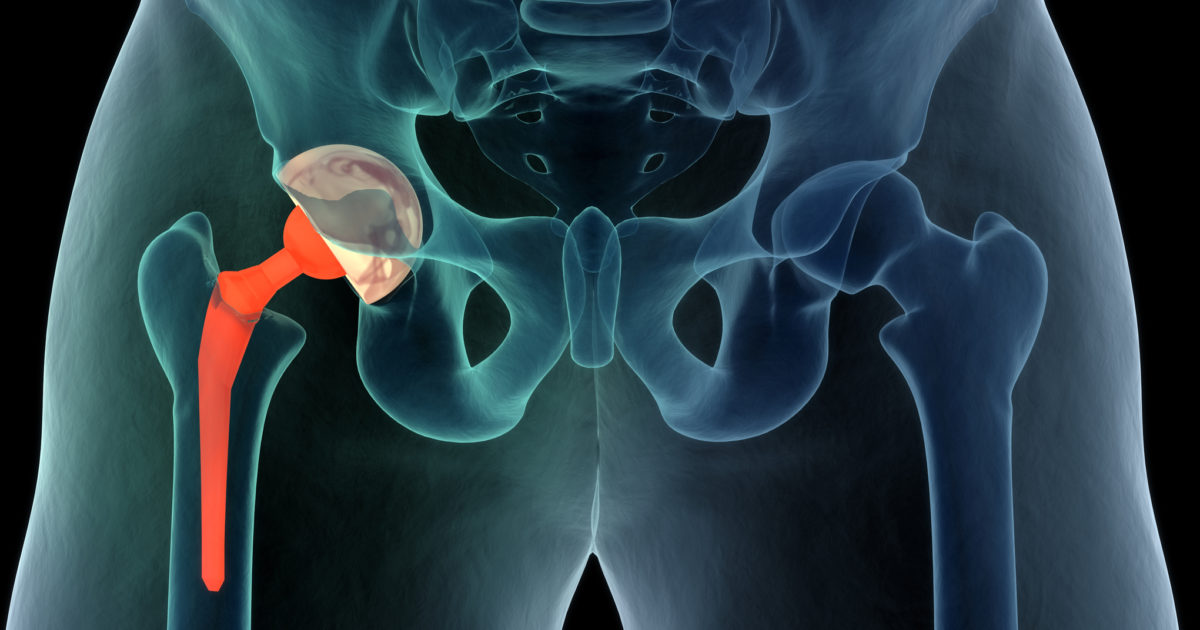

During hip replacement, a surgeon removes the damaged sections of your hip joint and replaces them with parts usually constructed of metal, ceramic and very hard plastic. This artificial joint (prosthesis) helps reduce pain and improve function.

Also called total hip arthroplasty, hip replacement surgery in Hyderabad might be an option for you if your hip pain interferes with daily activities and nonsurgical treatments haven't helped or are no longer effective. Arthritis damage is the most common reason to need hip replacement.